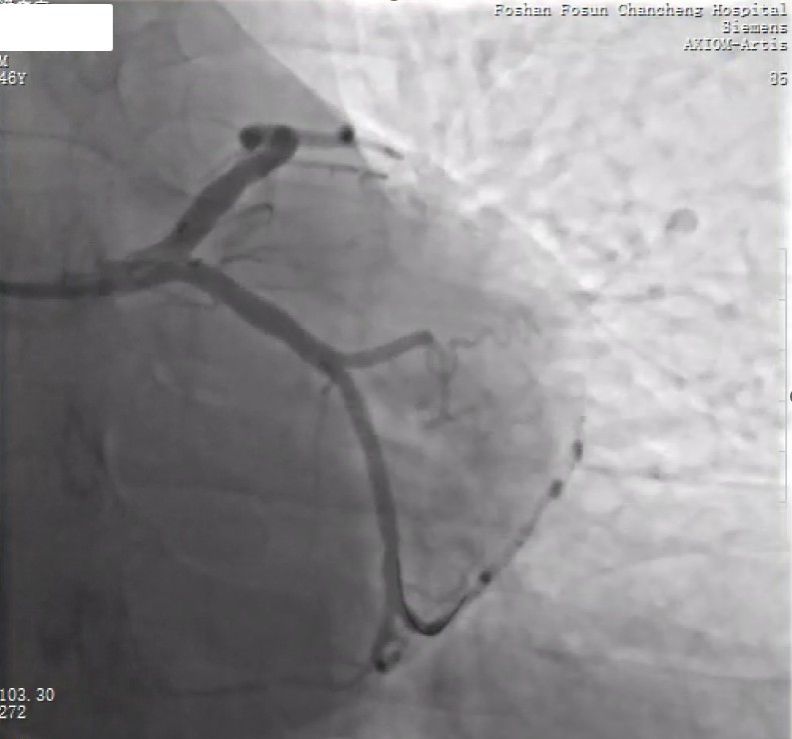

植入Freesolve 3.0/18可降解支架

复查OCT,支架贴壁膨胀均较好